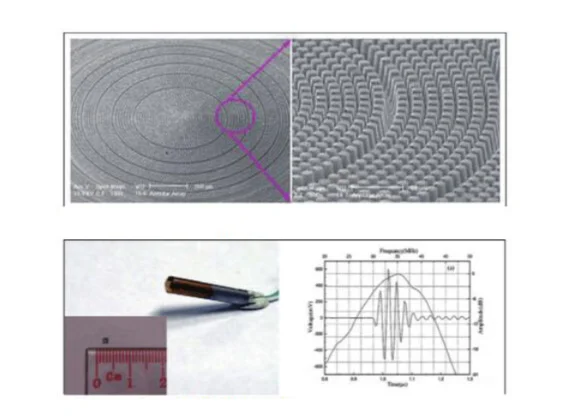

For Compatible GE: Logiq 7 Logiq9 Logiq A5 Logiq P5 Logiq S6 Vivid 7 Expert Vivid 7 Pro Convex Array Abdominal Probe 4C